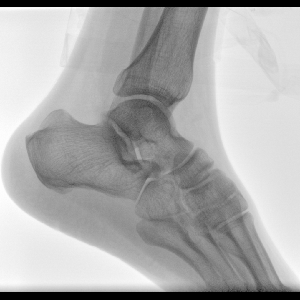

Clinical picture

临床图片